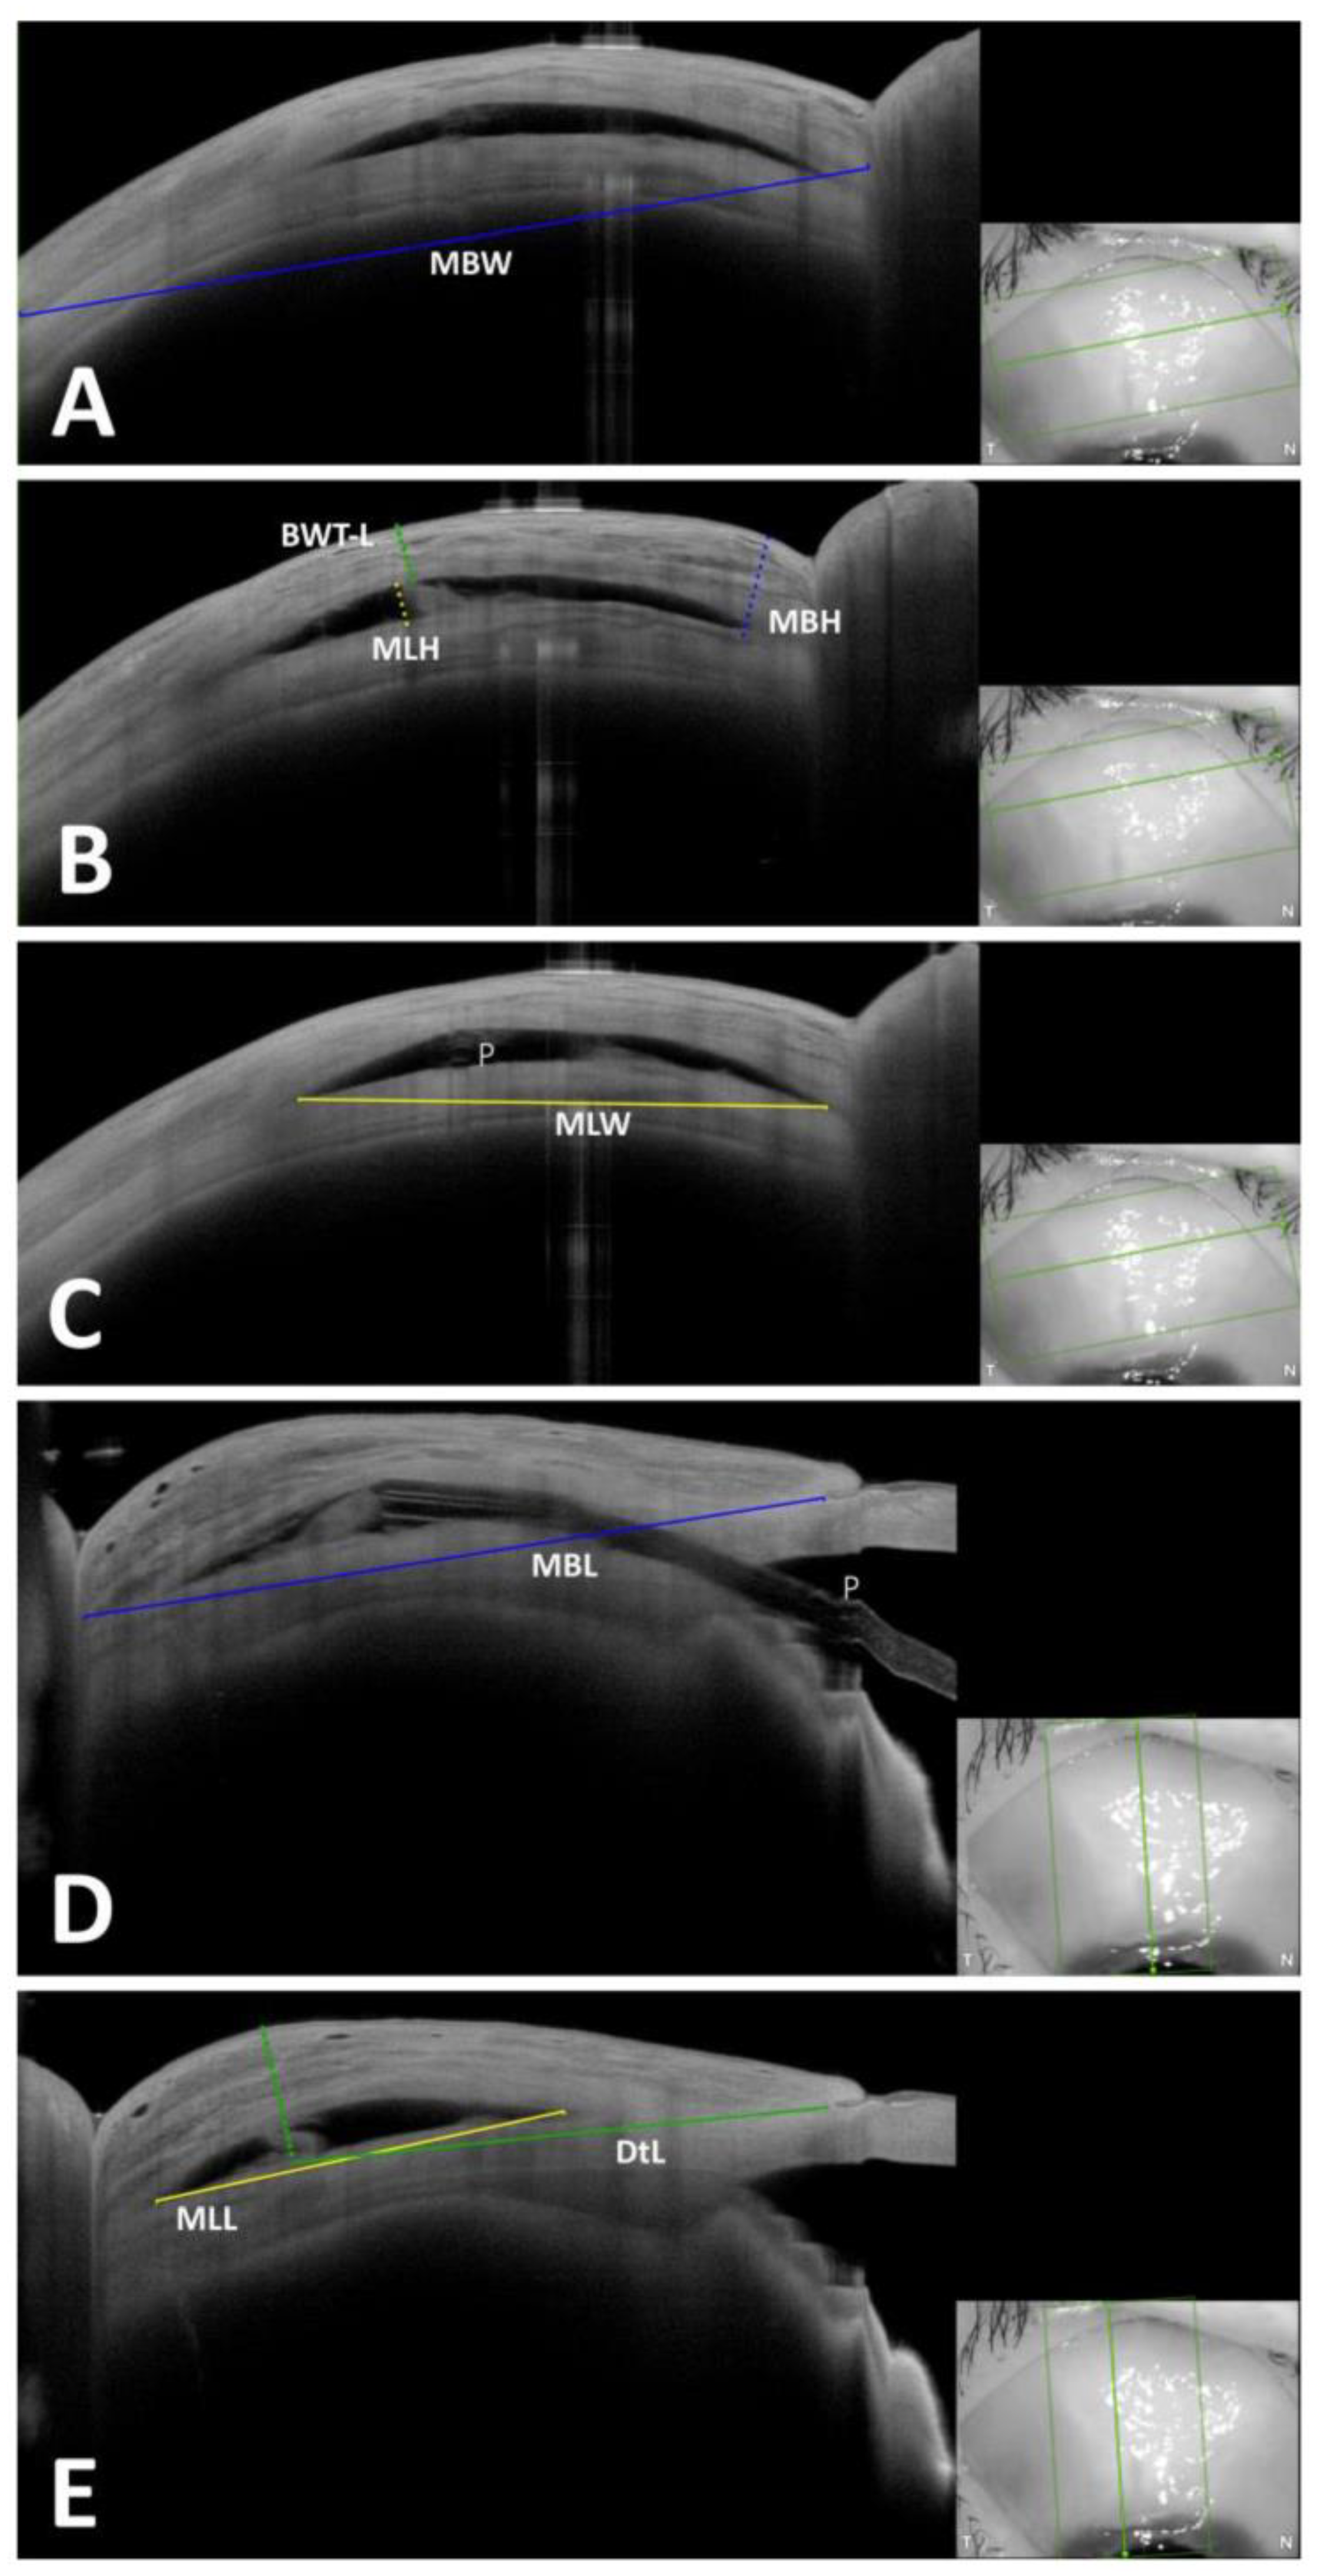

| Maximum Bleb Height | MBH | The maximum height of the bleb seen in the tangential scans, measured as the maximum perpendicular distance from the sclera to the first reflex at the conjunctiva. | |

| Maximum Bleb Width | MBW | The maximum width of the bleb seen in tangential scans, measured as a direct line between two points: the beginning of changes in tenon thickness nasally to the end of the tenon changes temporally. | If the whole width of the bleb could not be captured in a single image, the maximum visible width was measured. |

| Maximal Bleb Length | MBL | The maximum posterior extension of the bleb seen in radial scans, measured as a direct line between two points: from the first changes in tenon thickness anteriorly to the last visible tenon change posteriorly. If the bleb extended over the cornea, measurement was started at the level of the scleral spur. | If the whole length of the bleb could not be captured in a single image, the maximum visible length was measured. |

| Maximum Lake Height | MLH | The maximum height of the episcleral lake (ES1 according to JBGS) in the tangential scans, measured as the maximum perpendicular distance from the inferior to the superior edge of the episcleral lake. | MLH was measurable only in blebs showing the pattern ES1 |

| Maximum Lake Width | MLW | The maximum width of the episcleral lake seen in tangential scans, measured as a direct line between two points: the beginning of the episcleral lake nasally to its end temporally. | MLW was measurable only in blebs showing the ES1-Pattern |

| Maximal Lake Length | MLL | The maximum posterior extension of the episcleral lake seen in a radial scan, measured as a linear distance between two points: the beginning of the episcleral lake anteriorly to its end posteriorly. | If the whole length of the episcleral lake could not be captured in a single image, the maximum visible length was measured. |

| Bleb Wall Thickness at the Lake | BWT-L | Minimal thickness of the bleb wall at the scan with the MLH, measured as the minimal perpendicular distance between the end of the episcleral lake and the first reflex at the conjunctiva. | BWT was measurable only in blebs showing the ES1-Pattern |

| Distance to Limbus | DtL | The linear distance between two points: point of corneal surface corresponding to the scleral spur and the point of the scleral surface corresponding to the highest point of the bleb in radial scans. |